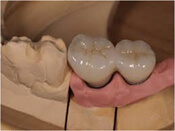

step7.プロビジョナルレストレーション装着

最終的な土台と被せ物を作る

仮歯を入れて咬み合わせなど機能面や審美面に問題がないか確認します。

また型取りして製作した模型の精度に問題がないかをチェックします。

模型の精密さ、歯の機能面・審美面に問題がなければ最終的な土台と被せ物を作ります。

step8.アバットメント・セラミック冠装着

チタン製の土台とセラミック冠をつける

仮の歯を使って問題なければ、チタン製の土台とセラミック冠をつけます。

まずチタン製の土台を規定の力で締結し、その上にセラミック冠を被せます。